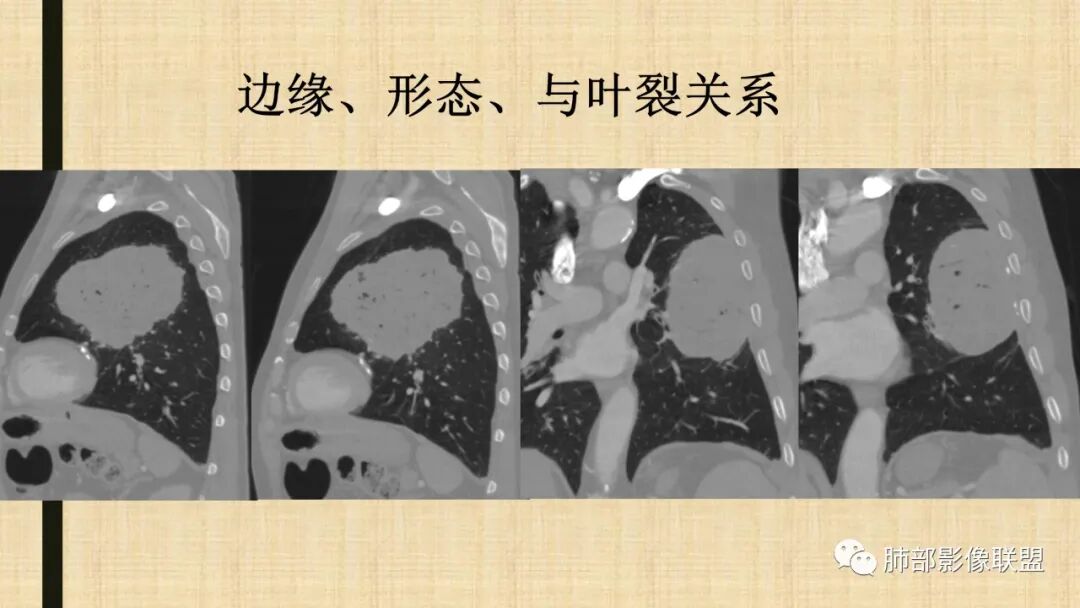

左肺上叶胸膜下肿块,宽基底与胸膜相连,跨叶裂,边缘清晰膨隆,其内支气管充气,部分扩张、僵直,无明显强化,血管造影征,考虑淋巴瘤,鉴别腺癌

左肺胸膜下巨大占位,跨叶裂,宽基底与胸膜相连,胸膜钙化,平扫密度较低,强化不明显,可见内部血管显影,支气管充气征和扩张,考虑为恶性,倾向于淋巴瘤

左肺上叶肿块,宽基底与胸膜相连,跨叶裂,边缘清晰膨隆,可见小分叶,其内支气管充气,部分扩张、僵直,呈枯枝征,支气管达边征,增强无明显强化,可见血管造影征,考虑恶性病变,淋巴瘤,鉴别粘液腺癌。

大肿块,边缘光滑,深分叶

近端支气管堵塞、推移为主

部分类似于脐凹征

大肿块、表面光滑但深分叶,肺门侧支气管堵塞

1)部位:周围型或中央型软组织肿块,以周围型为多见,且肿瘤多位于肺上叶。如本例:该肿瘤位于左肺上叶。

3)肿块边界和边缘:多较清楚,呈圆形、类圆形,且由于肿块生长速度不均匀,可见分叶,毛刺少见。有报道肿块周围毛玻璃影是多形性癌特征表现。